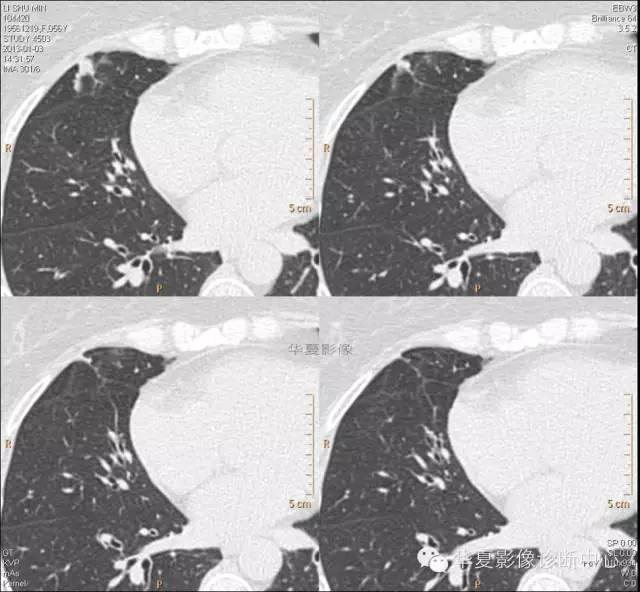

【病例学习】典型周围型肺癌CT病例一例

女,56岁,其父因肺癌去世,自觉胸部疼痛不适来诊要求拍胸片。